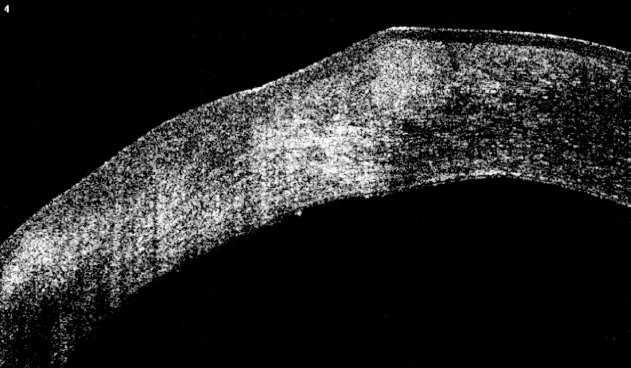

On the 4th day after surgery partial epithelialization of the ulcerative defect, a decrease in the folds of the descemet membrane and resorption of corneal edema were noted (Fig. 4).

Fig. 4. Photo of the anterior segment with fluorescein 4 days post-op in patient O.: a — color mode; b — angiography mode of retinal camera

Рис. 4. Фотография переднего отрезка глаза пациентки О. с применением флуоресцеина через 4 дня после операции: a — в цветном режиме; b — в режиме флуоресценции

After 1 week the patient was discharged with a visual acuity of 0.1 in the left eye and was not corrected. According to OCT data a decrease in corneal thickness to 541–559 microns was detected due to resorption of edema of the stroma and epithelium, while the epithelium is uneven.